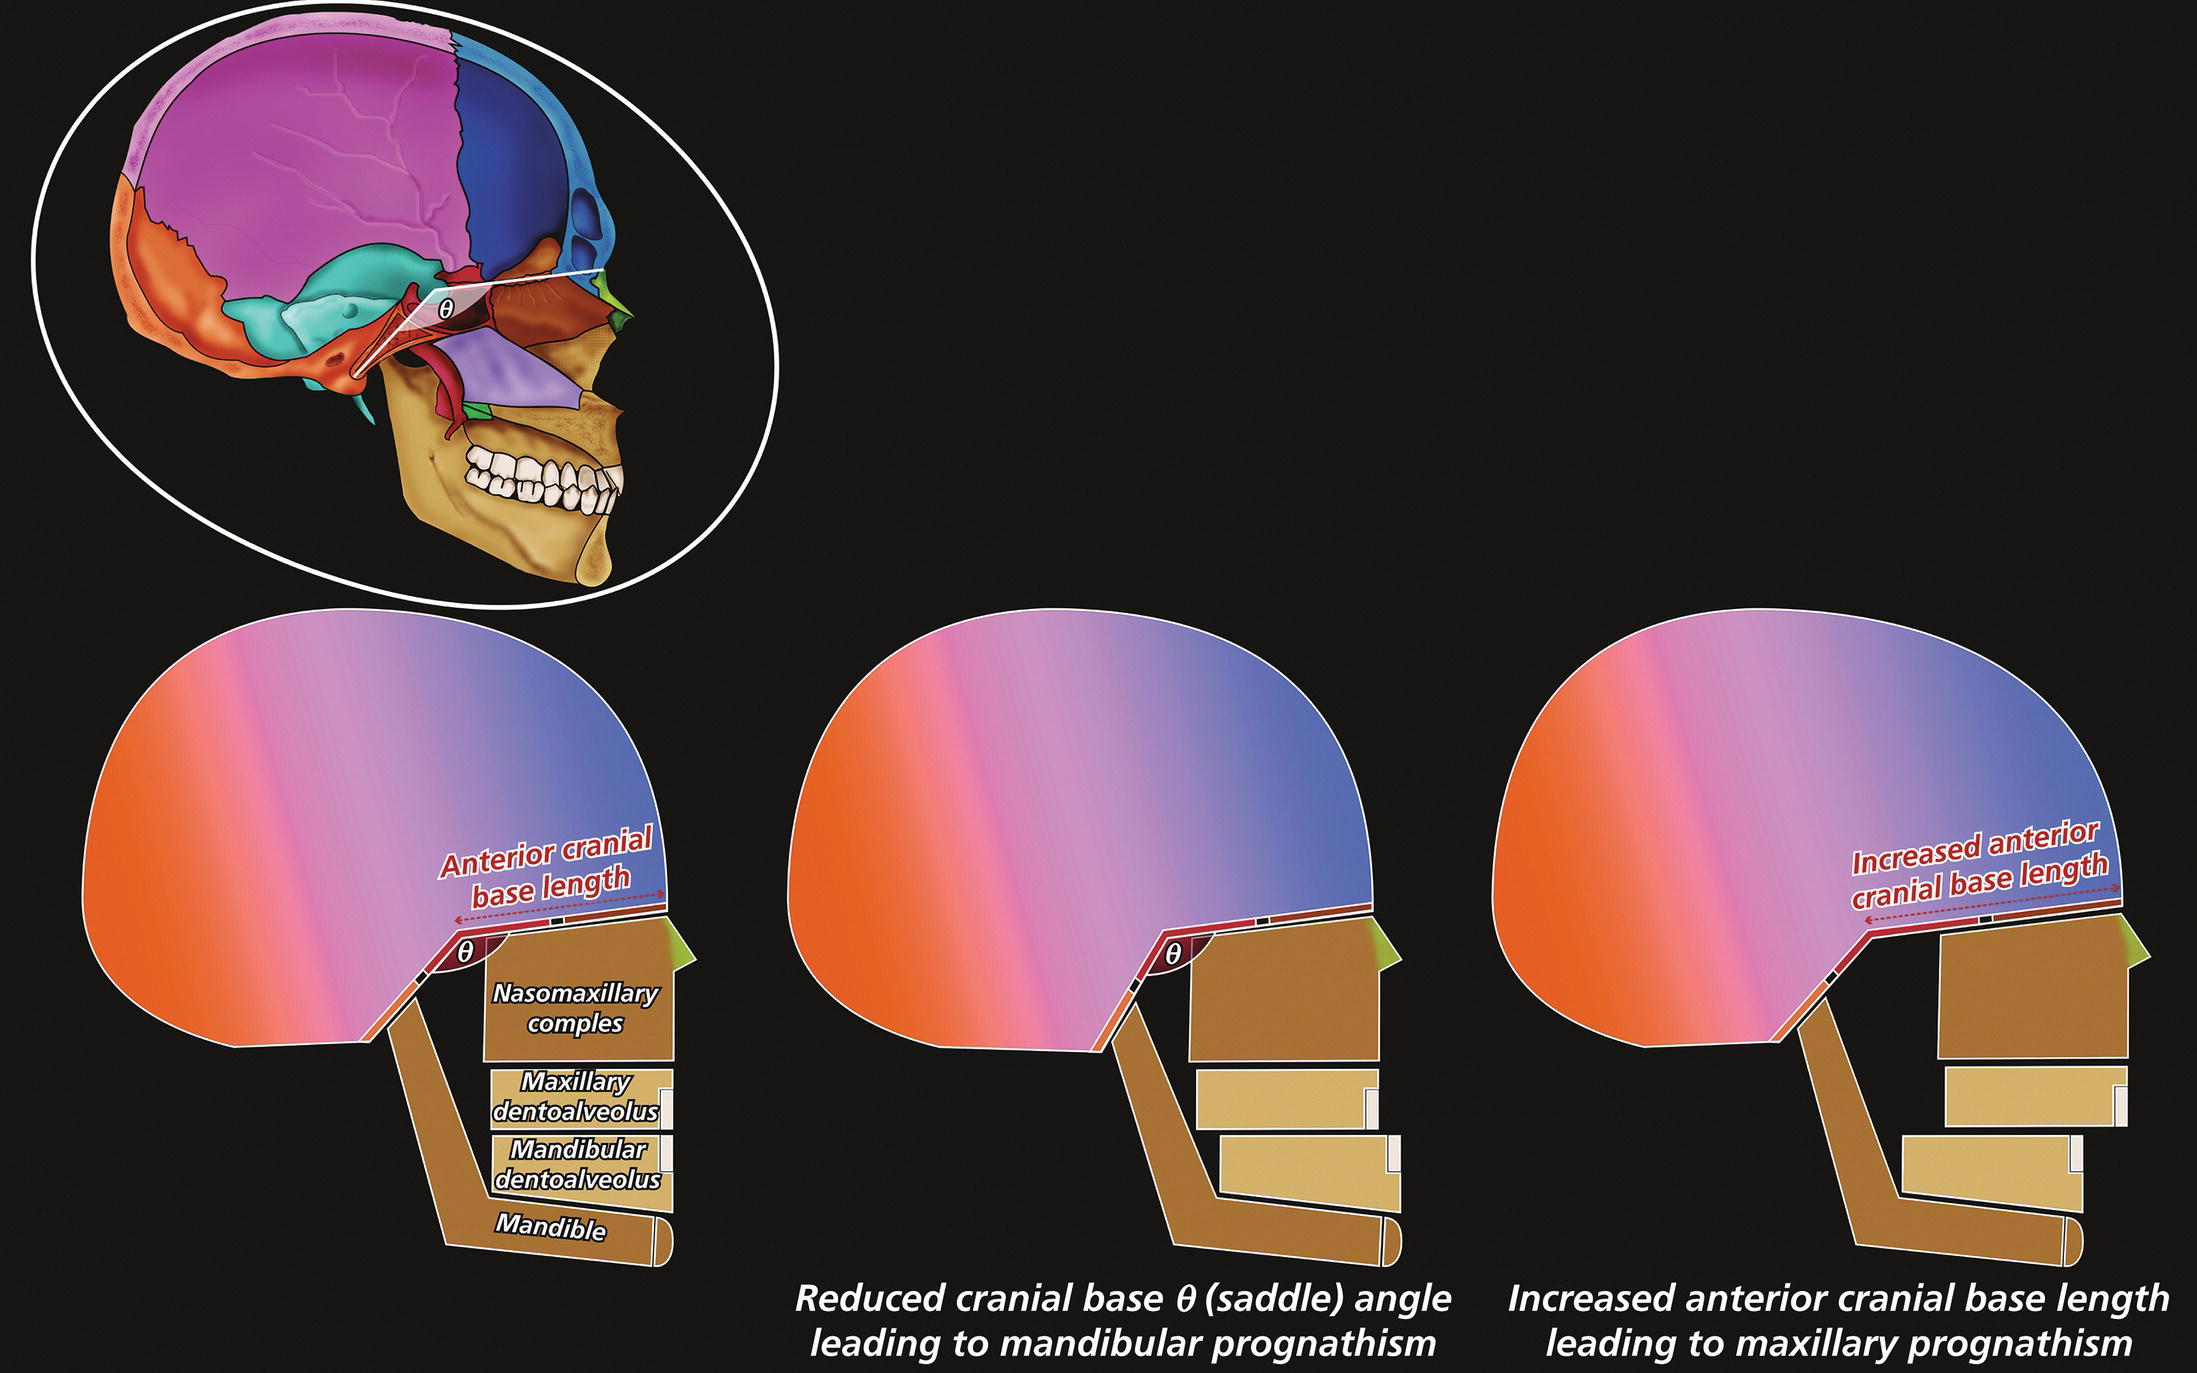

Cranial base angle (Figure 8.13)

Anterior cranial base length (Figure 8.13)